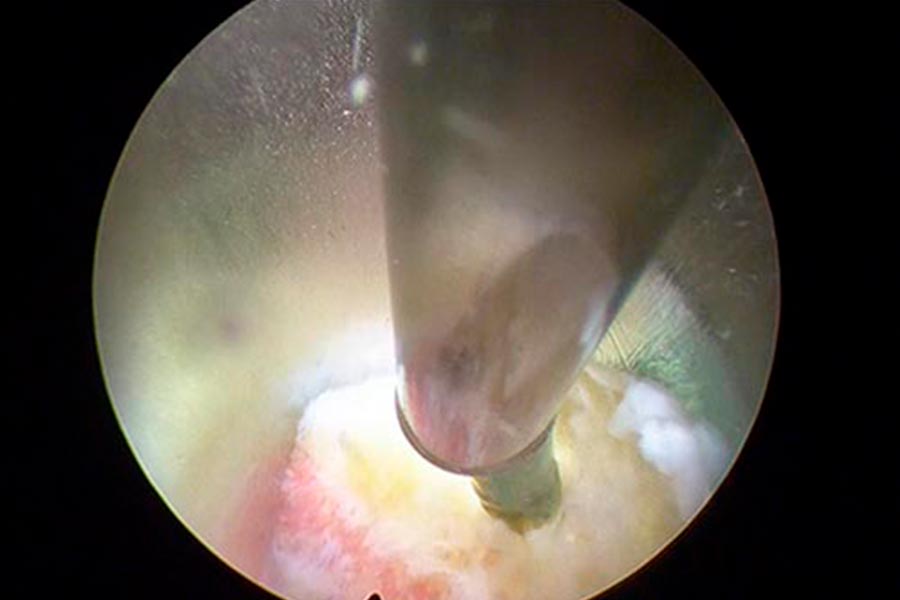

Caso clínico: endoscopia de columna multinivel L4L5 y L5S1

Durante la intervención quirúrgica, se abordarán los dos niveles mediante la técnica de endoscopia de columna.

Mediante una incisión mínima en la piel de 2-3 milímetros, el equipo de ICAC tratará a una paciente joven que sufre una una hernia discal en L4L5 y L5S1.